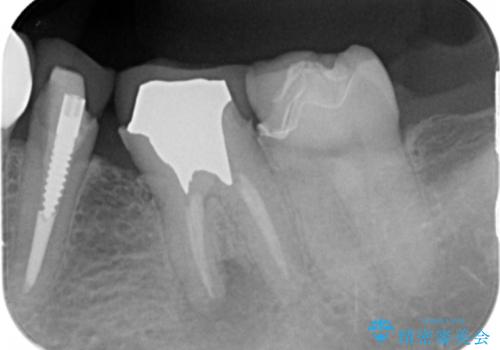

- 奥歯の被せ物をセラミックにしたいとご希望され、来院された患者様です。

左下の奥歯(左下6)の劣化した白い被せ物と金属の土台を除去し、セラミッククラウンによる補綴治療を行いました。

- ¥286,000 (根管治療、土台、仮歯、クラウン) ※税込費用は治療当時の料金となります